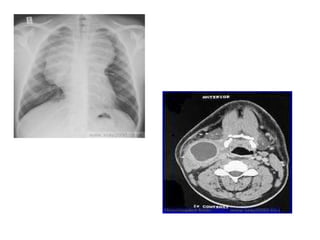

Imaging Workup

• CXR if malignancy sus.

– To look for mediastinal lymphadenopathy

• Ultrasound

– Abscess?

– Benign vs. malignant

• Sometimes CT/MRI

– To evaluate for abscess

A study found that multidetector computed tomography (MDCT)

imaging was very useful in determining the morphology

(cellulitis with a few small subcutaneous nodules and channels)

and the extension of the lesion in a case of nodular lymphangitis

caused by Mycobacterium marinum